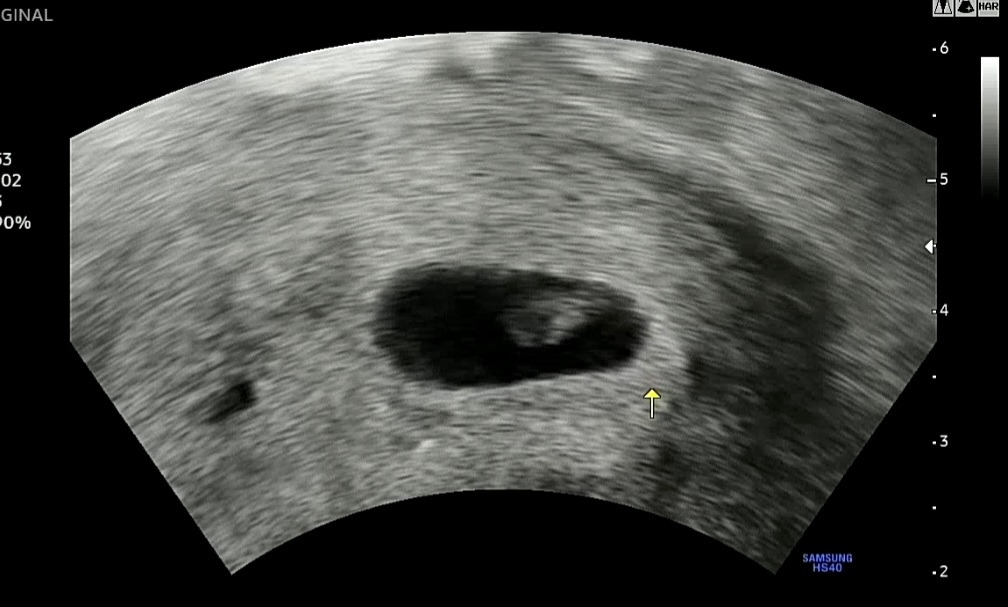

초음파 사진 속의 너는 타원형 UFO를 타고 온 외계인처럼 내 몸속에 날아들었더라.

팔딱팔딱 심장 뛰는 걸 처음 본 5월3일(6주3일)엔 안도의 한숨과 기쁨의 눈물을 함께 흘렸단다.

4밀리미터의 존재감을 확실하게 보여주는 널 보면서 기쁘고 흐뭇하고 대견하기까지 하더라.

Screenshot_20220905-164227_Gallery (1).jpg